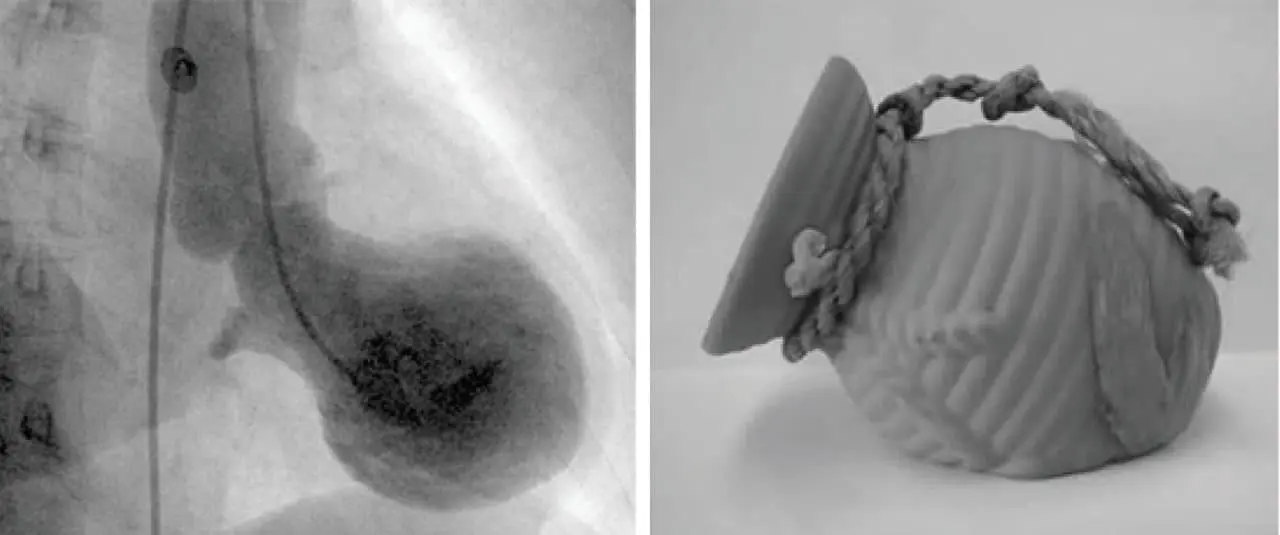

Кардиомиопатия такоцубо, известная также как «синдром разбитого сердца», является особой формой временной дисфункции сердечной мышцы, при которой наблюдается характерное расширение и округление верхушки левого желудочка. Именно эта форма, напоминающая ловушку для осьминогов — такоцубо — легла в основу японского наименования заболевания. На фоне подобного состояния пациенты обычно ощущают внезапную сильную боль в груди, одышку, а иногда и кратковременную потерю сознания. Клиническая картина и электрокардиографические данные часто схожи с признаками инфаркта миокарда, поэтому для точной диагностики применяются дополнительные методы обследования, такие как коронароангиография и ультразвуковое исследование сердца.